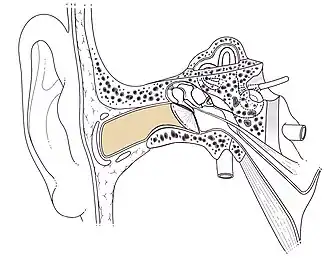

Conduit auditif externe droit Schéma